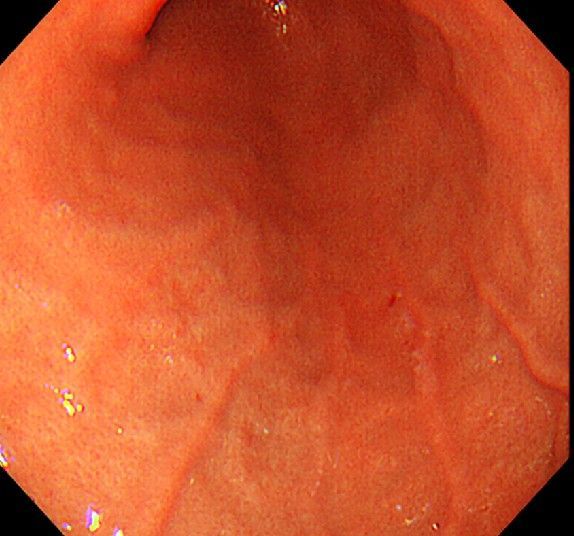

위 내시경을 찍었는데 위염 종류 사진을 알 수 있을까요? (사진 많습니다..)

한달 전 쯤에 소화불량과 속쓰림이 3개월 동안 약을 먹어도 낫지 않아 위 내시경을 찍었는데 위에 염증이 많이 있다는 이야기를 들었습니다...그런데 상태가 얼마나 안 좋은지 어떤 종류의 위염인지에 대해서는 물어봐도 안 알려주셔서 여기에라도 올려서 여쭈어봅니다... 제 상태가 얼마나 심각한 걸까요..

사진상으로 보아서는 정상에 가까운 점막상태이거나 약간의 표재성 위염이 있는 정도로 보입니다.

홍반성 위염이 있으며 경증의 역류성 식도염이 있습니다